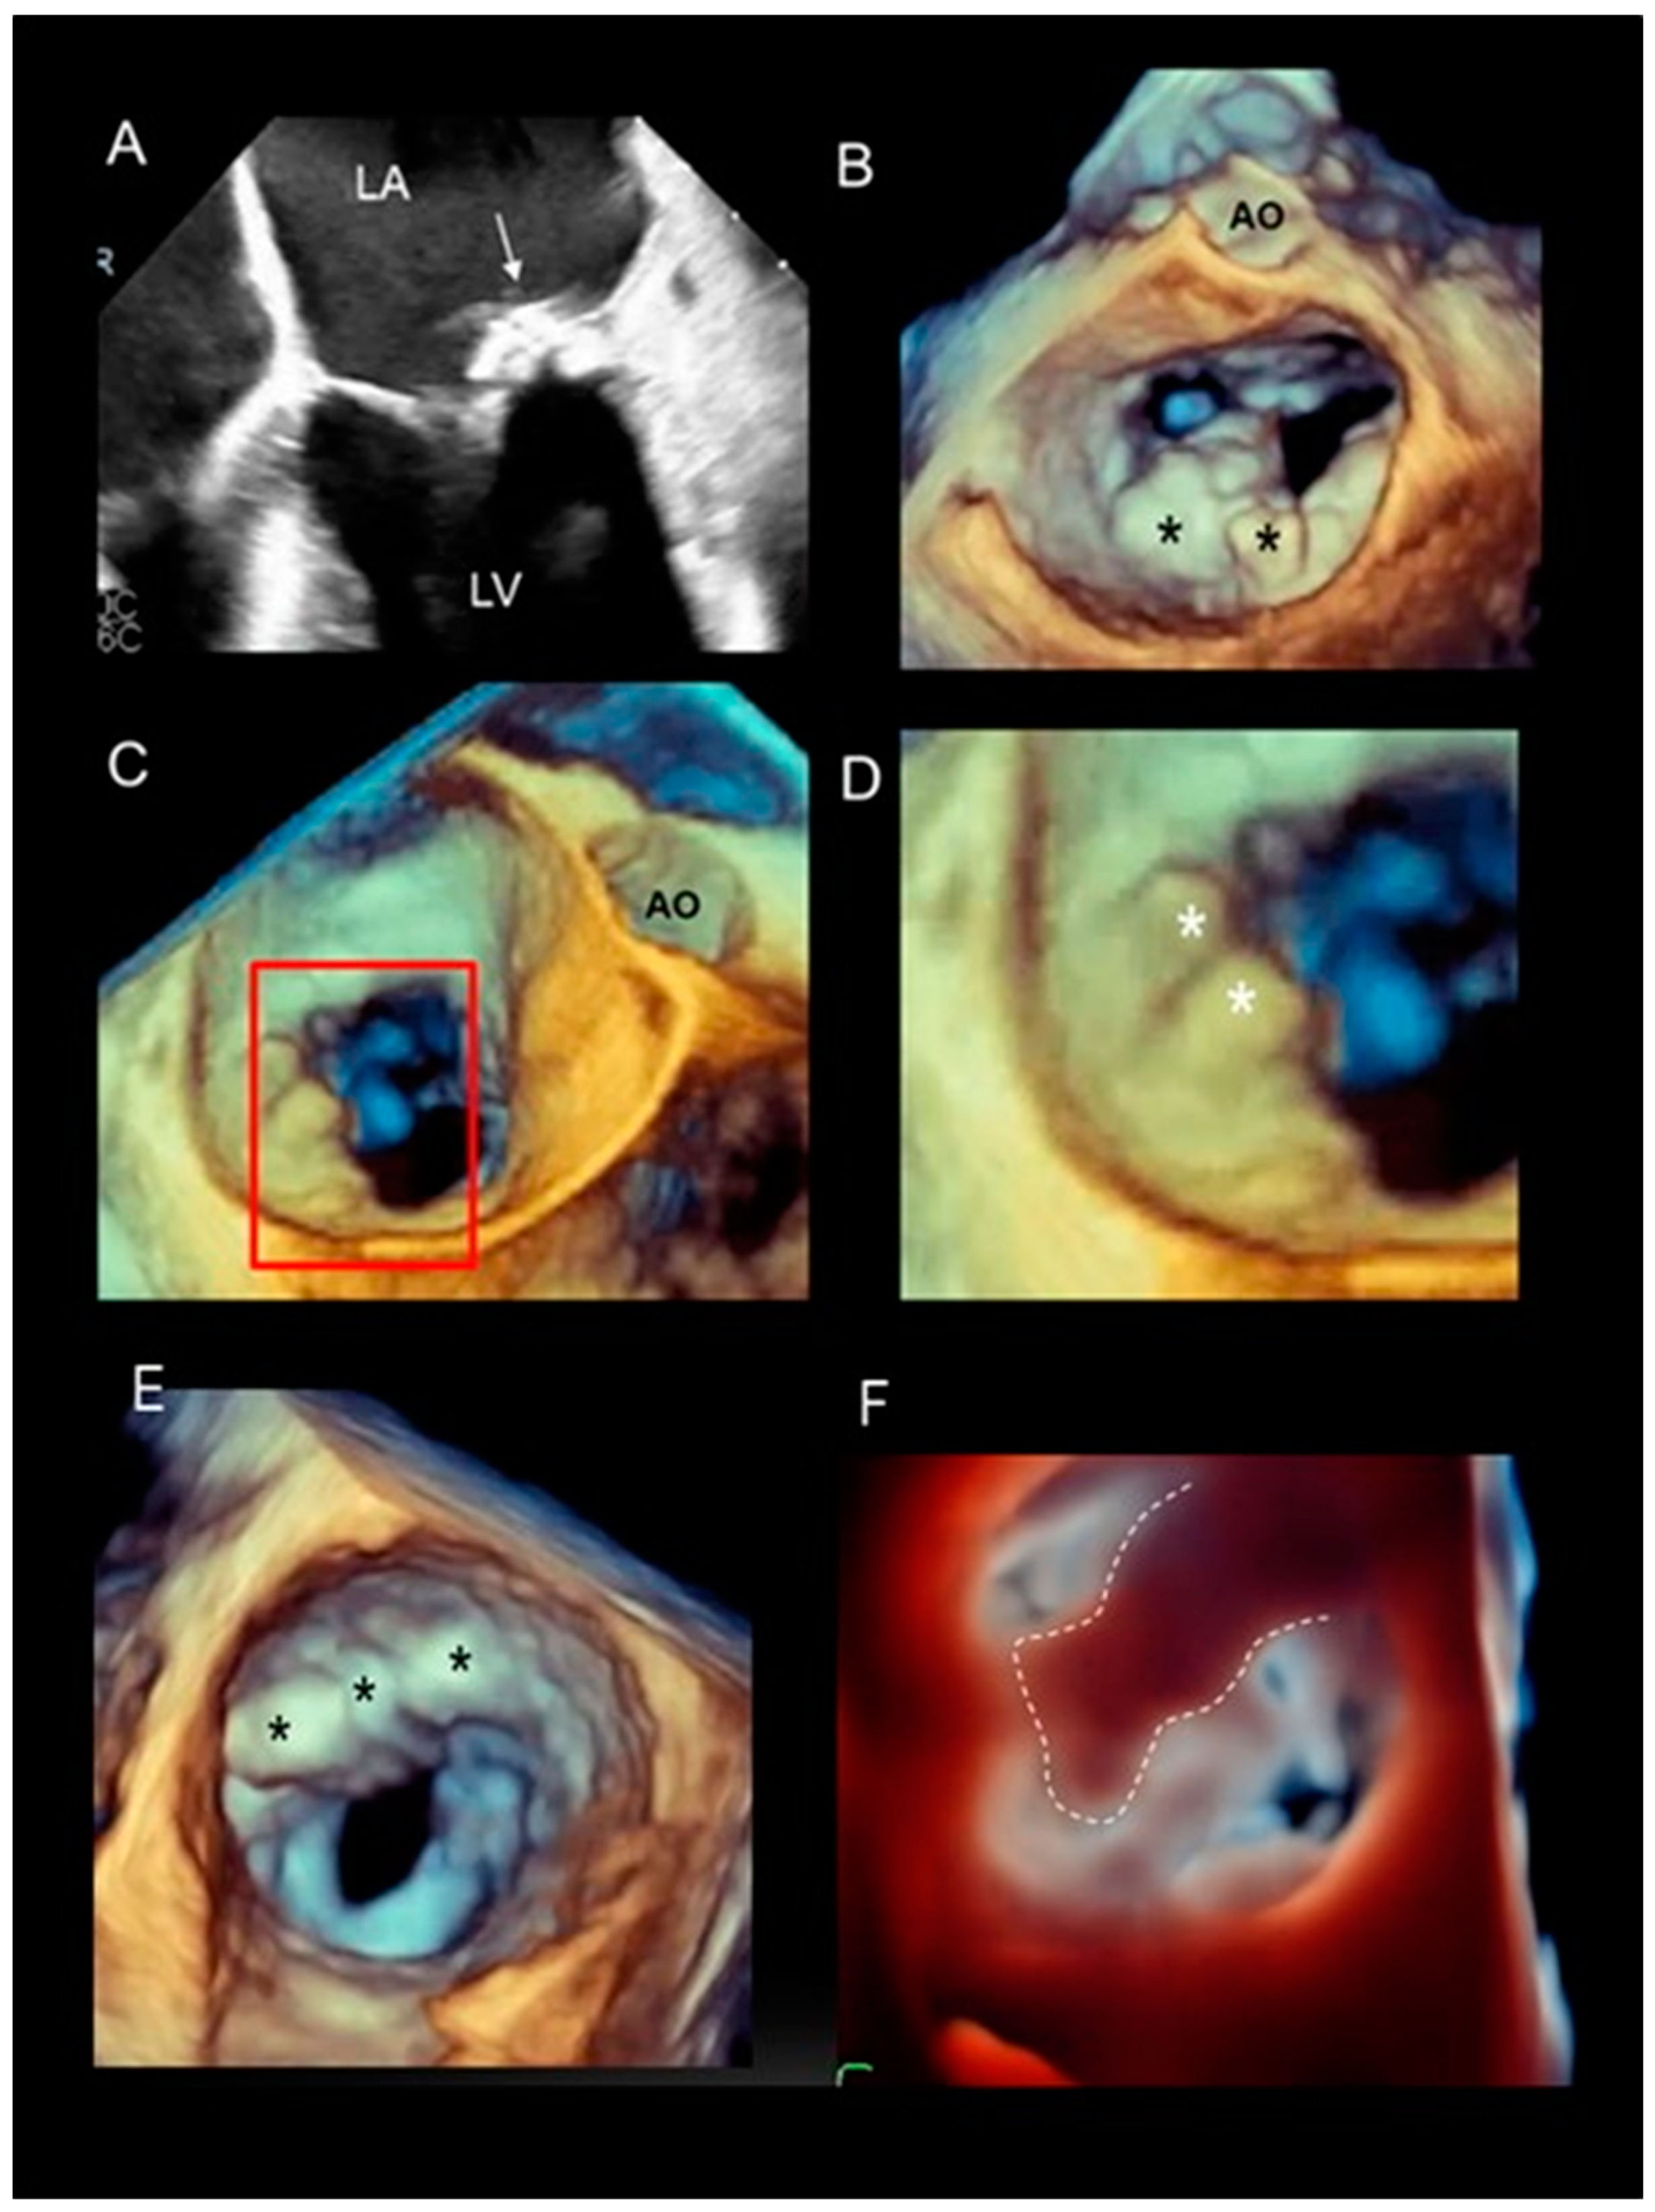

Mitral Annular Calcification

- Churchill, T.W.; Yucel, E.; Deferm, S.; Levine, R.A.; Hung, J.; Bertrand, P.B. Mitral Valve Dysfunction in Patients with Annular Calcification: JACC Review Topic of the Week. J. Am. Coll. Cardiol. 2022, 80, 739–751. [Google Scholar] [CrossRef]

- Faletra, F.F.; Leo, L.A.; Paiocchi, V.L.; Caretta, A.; Viani, G.M.; Schlossbauer, S.A.; Demertzis, S.; Ho, S.Y. Anatomy of mitral annulus insights from non-invasive imaging techniques. Eur. Heart J. Cardiovasc. Imaging 2019, 20, 843–857. [Google Scholar] [CrossRef]